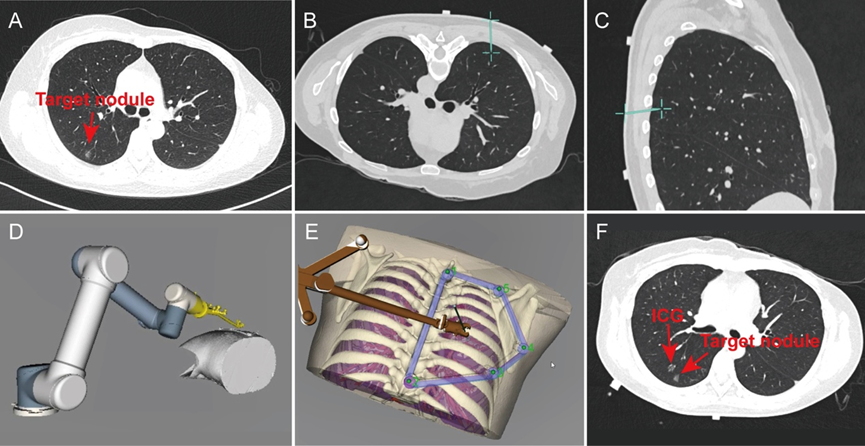

图:基于机器人导航系统的经皮肺结节定位

图片

图:肺部CT扫描与三维重建

图:导航路径规划与机器人辅助定位穿刺过程